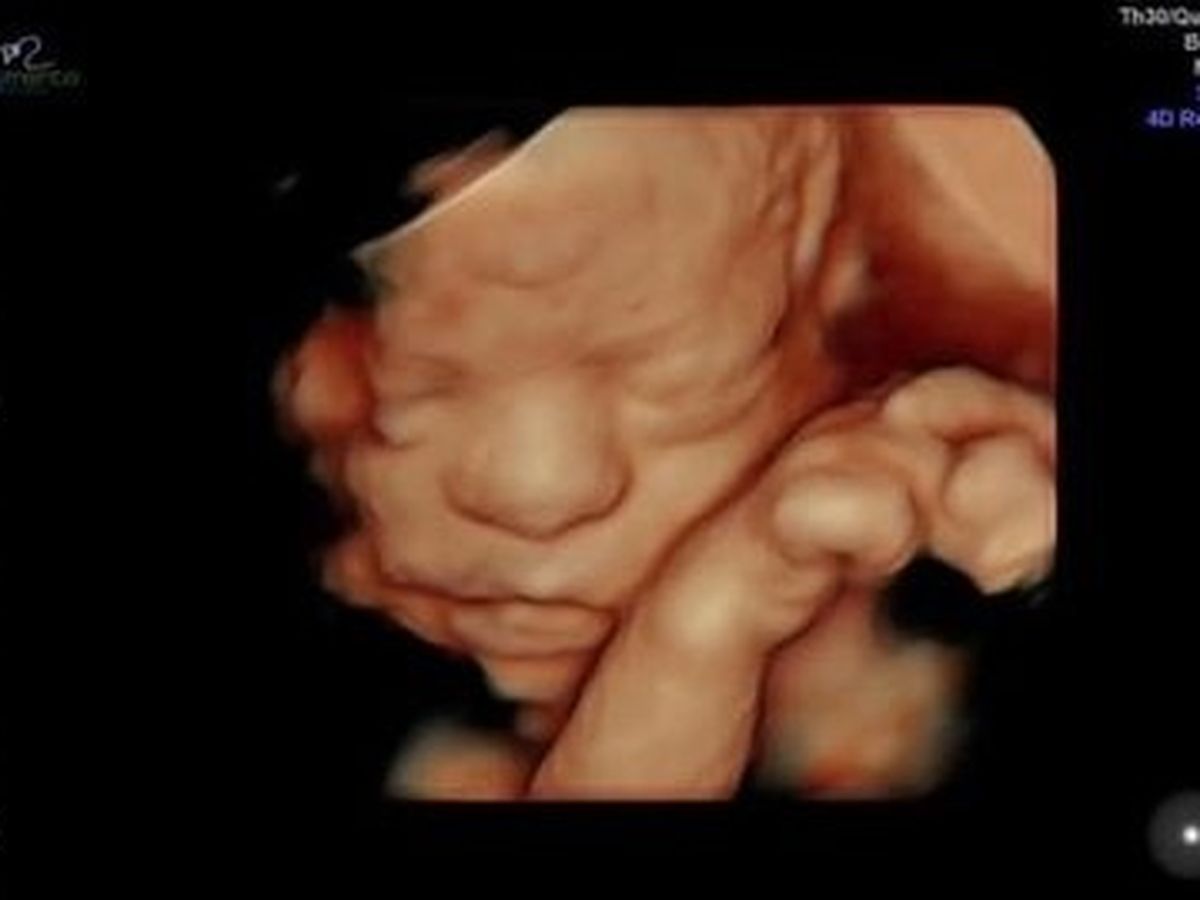

On Tuesday August 25th at 36 weeks pregnant, my son and his wife found out that their 1st child, a baby girl, Nala Jhené Brown, would only live for 1-2 mins after birth and then she would die. She has a rare condition, Right-sided congenital diaphragmatic hernia (RCDH), as well as heterotaxy. This has caused her intestines to invade her upper cavity. By doing so, her lungs did not fully develop. She has no left lung and only a very tiny sliver of a right lung. On top of that, some of her organs were swapped and developed on the opposite side of her body making it an even more rare case conjoined. The expert doctors at UCSF did a fetus MRI and this is where the finding resulted in a decision that they would not intervene once she is born. She simply does not have enough lung to survive.